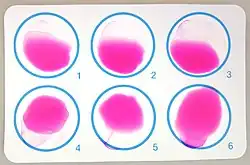

- Demonstration of antibodies against the agent, either with the classic Huddleson, Wright, and/or Bengal Rose reactions, either with ELISA or the 2-mercaptoethanol assay for IgM antibodies associated with chronic disease

Definite diagnosis of brucellosis requires the isolation of the organism from the blood, body fluids, or tissues, but serological methods may be the only tests available in many settings. Positive blood culture yield ranges between 40 and 70% and is less commonly positive for B. abortus than B. melitensis or B. suis. Identification of specific antibodies against bacterial lipopolysaccharide and other antigens can be detected by the standard agglutination test (SAT), rose Bengal, 2-mercaptoethanol (2-ME), antihuman globulin (Coombs') and indirect enzyme-linked immunosorbent assay (ELISA). SAT is the most commonly used serology in endemic areas.[21][22] An agglutination titre greater than 1:160 is considered significant in nonendemic areas and greater than 1:320 in endemic areas.

Due to the similarity of the O polysaccharide of Brucella to that of various other Gram-negative bacteria (e.g. Francisella tularensis, Escherichia coli, Salmonella urbana, Yersinia enterocolitica, Vibrio cholerae, and Stenotrophomonas maltophilia), the appearance of cross-reactions of class M immunoglobulins may occur. The inability to diagnose B. canis by SAT due to lack of cross-reaction is another drawback. False-negative SAT may be caused by the presence of blocking antibodies (the prozone phenomenon) in the α2-globulin (IgA) and in the α-globulin (IgG) fractions.